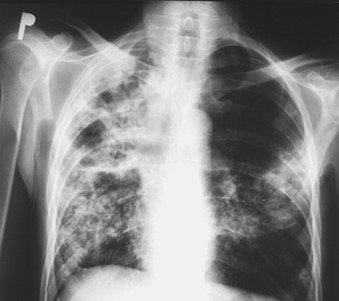

Chest x-ray showing dense opacity pleural effusion in the lower left lung of primary pulmonary TB

Pulmonary tuberculosis affects the lungs and often causes symptoms such as a chronic cough that lasts up to 3 weeks or more, chest pain, blood in cough (hemoptysis), weight loss, low-grade fever, and night sweats. When the infection spreads to other parts of the body, it is known as secondary tuberculosis.

It tends to be more severe, with a more significant immune response and the potential for forming cavities in the upper part of the lungs. Active TB disease can also cause the infection to disseminate to other organs, such as the spine, the central nervous system, or the bowel.